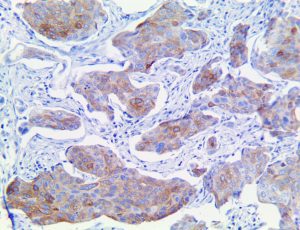

It is the ICU physician who is most likely to witness one of the deadliest manifestations of the abnormal immunological response, the cytokine storm syndrome (CSS). This response is also referred to by some as the cytokine release syndrome (CRS). CSS is characterized by continuous activation and expansion of macrophage and lymphocyte populations, which secrete large amounts of cytokines, causing the cytokine storm. This massive cytokine release is akin to hemophagocytic lymphohistiocytosis (HLH) disease, a syndrome characterized by initial unchecked and persistent activation of cytotoxic T lymphocytes and NK cells.

Clinical and laboratory manifestations of HLH include fever, enlarged liver and/or spleen, neurologic dysfunction, coagulopathy, liver dysfunction, cytopenias (i.e., low levels of erythrocytes, leukocytes, and/or platelets), hypertriglyceridemia, hyperferritinemia, hemophagocytosis, and eventually diminished NK cell activity as the immune system becomes progressively paralyzed. HLH can be familial (primary HLH) or secondary to another disease process (sHLH), such as rheumatic disease, in which it is referred to as macrophage activation syndrome (MAS, characterized by elevated ferritin).